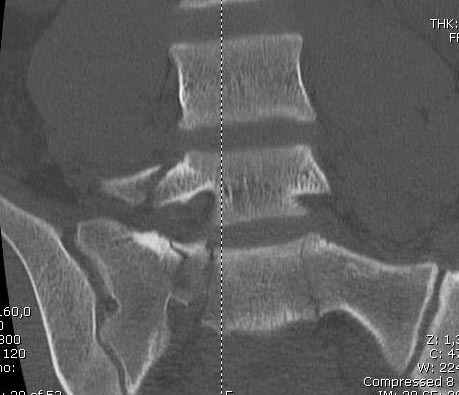

Здесь слайды случая больного с политравмой, включающей сегментарный перелом бедра и повреждение таза с нарушением тазового кольца, разрыв симфиза и перелома крестца зон 2 и 3.

На множественных слайдах важные моменты операции. Хотел бы подчеркнуть, как важно иметь возможности всех необходимых ренгенограмм, включая компютерную томографию и стандартных внутритазовых рентгенограмм (инлет и оутлет).